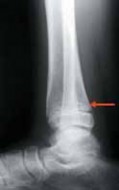

2. For a medially gapped Salter Harris type II abduction injury, a medial approach is used (

TECH FIG 1

).

A B CTECH FIG 1•

Surgical approach to a medially gapped fracture.

A.

This AP radiograph demonstrates a medially gapped Salter-Harris type II abduction-type fracture.

B.

A medial approach is used to obtain open reduction of this fracture.

C.

This operative photograph highlights the periosteum interposed in the physeal fracture, which was extracted to obtain anatomic reduction and prevent medial gapping.